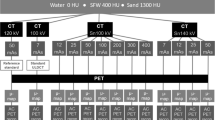

Measurements

All phantoms were scanned on a Biograph mCT PET-CT system with True V and 64 slice Definition A/S CT (Siemens Healthcare GmbH, Germany). For each of the four phantoms, 1 PET scan was acquired together with 5 CT scans, using CARE kV reference settings of 120 kV, 50 mAs (effective), and image quality optimised for non-contrast CT (point 3 on the sliding scale), with the phantom positioned in the centre of the gantry in x and y planes. Of the 5 CT scans performed for each phantom, 1 CT scan was performed with CARE kV on, whereby the scanner chose the kV and mAs combination giving the lowest dose to the patient, thus considered to be the optimal tube voltage. For the 4 remaining scans, CARE kV was operated in semi mode with tube voltages specified at 140, 120, 100 and 80 kV, with mAs modulated to provide the reference image quality, optimised for non-contrast-enhanced CT. A total of 5 attenuation-corrected PET reconstructions were made for each phantom, using the attenuation maps created from each of the 5 CT scans. A standard whole-body PET-CT oncology scan protocol template was used for all acquisitions, with the specific CT and PET acquisition and reconstruction protocol settings provided in Table 1, with axial scan ranges being identical for all 5 CT scans for a given phantom.

Effective mAs is used in protocols on Siemens CT systems. This is calculated by multiplying the tube current (mA) by the rotation time (s) and dividing this value by the pitch factor. With this protocol using a tube rotation time of 0.5 s and a pitch of 0.8 as shown in Table 1 together with the scanner’s minimum tube current of 20 mA, 13 is the lowest effective mAs deliverable by the system with use of this protocol.